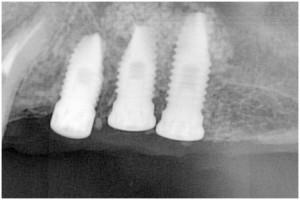

杉山3 埋入時杉山4 左上56サイナスリフト・拡大写真